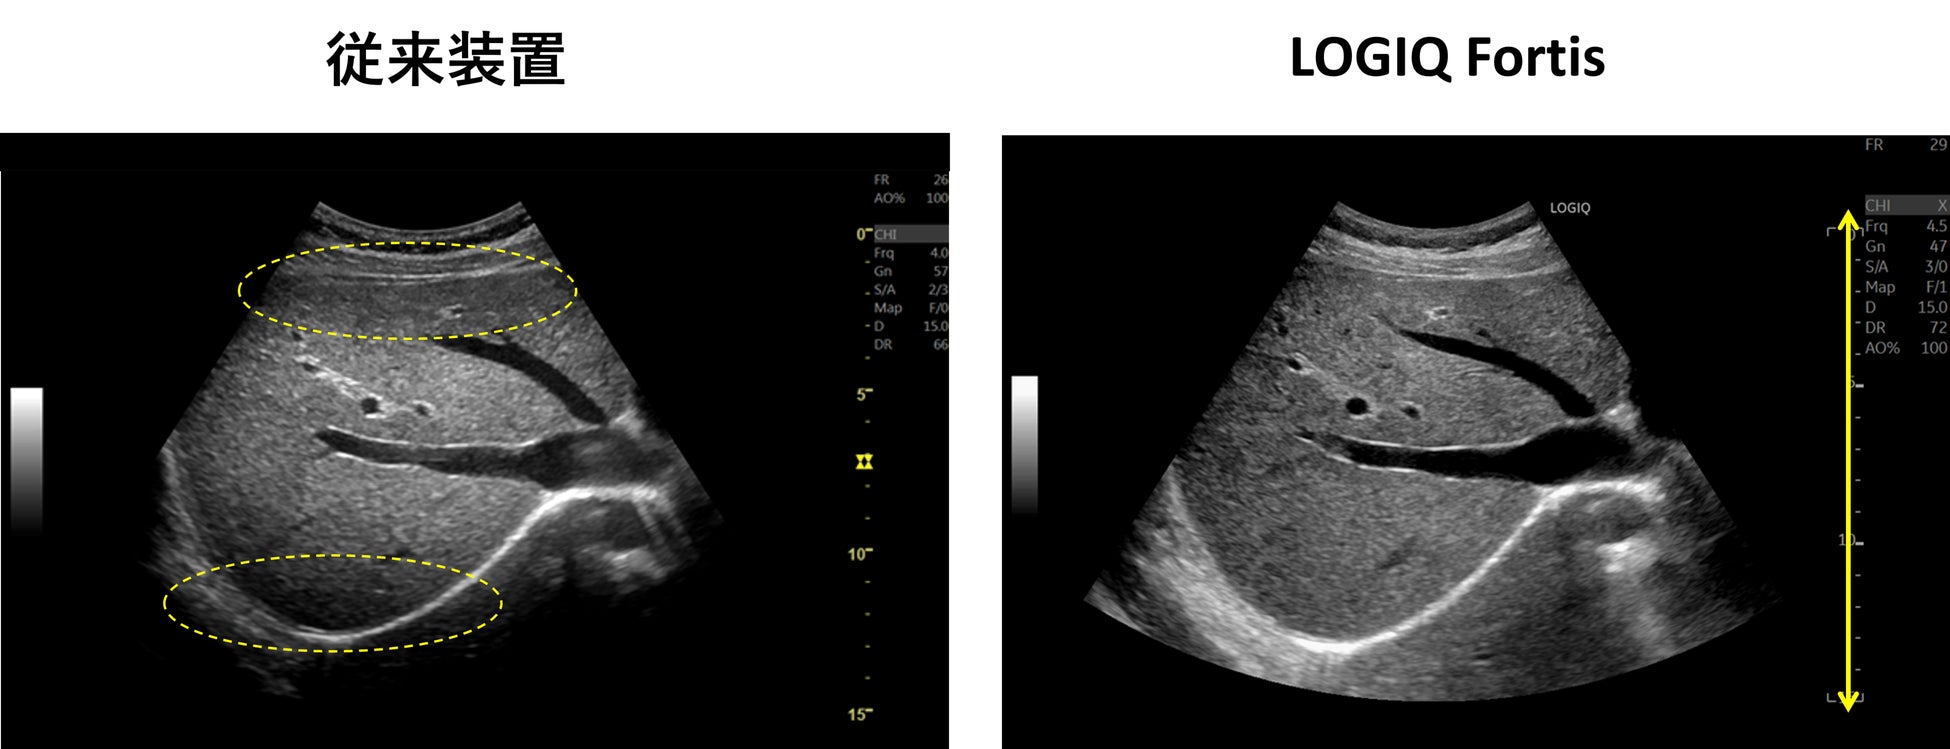

| 従来装置ではフォーカス近傍が明瞭に描出されているが、フォーカス以外の部分は明瞭に描出できておらず、関心領域に応じてフォーカスの位置を適宜変更する必要がある。LOGIQ Fortisでは、フルフォーカスにより浅部も深部も明瞭に描出され、フレームレートも高い。 |